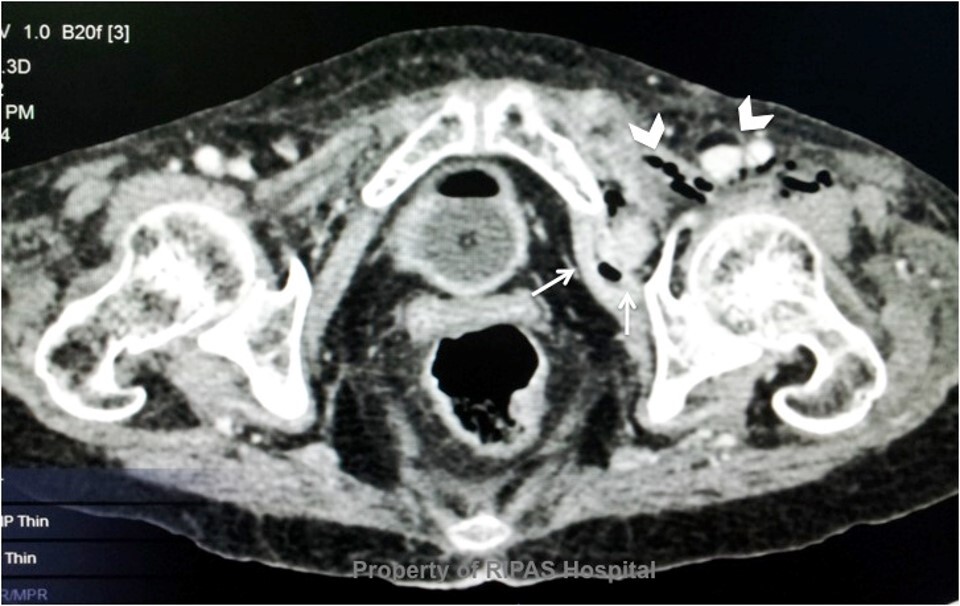

obturator hernia

A

-This extremely rare abdominal hernia happens mostly in women.

-This hernia protrudes from the pelvic cavity through an opening in the obturator foramen.

-This will not show any bulge but can act like a bowel obstruction and cause nausea and vomiting.